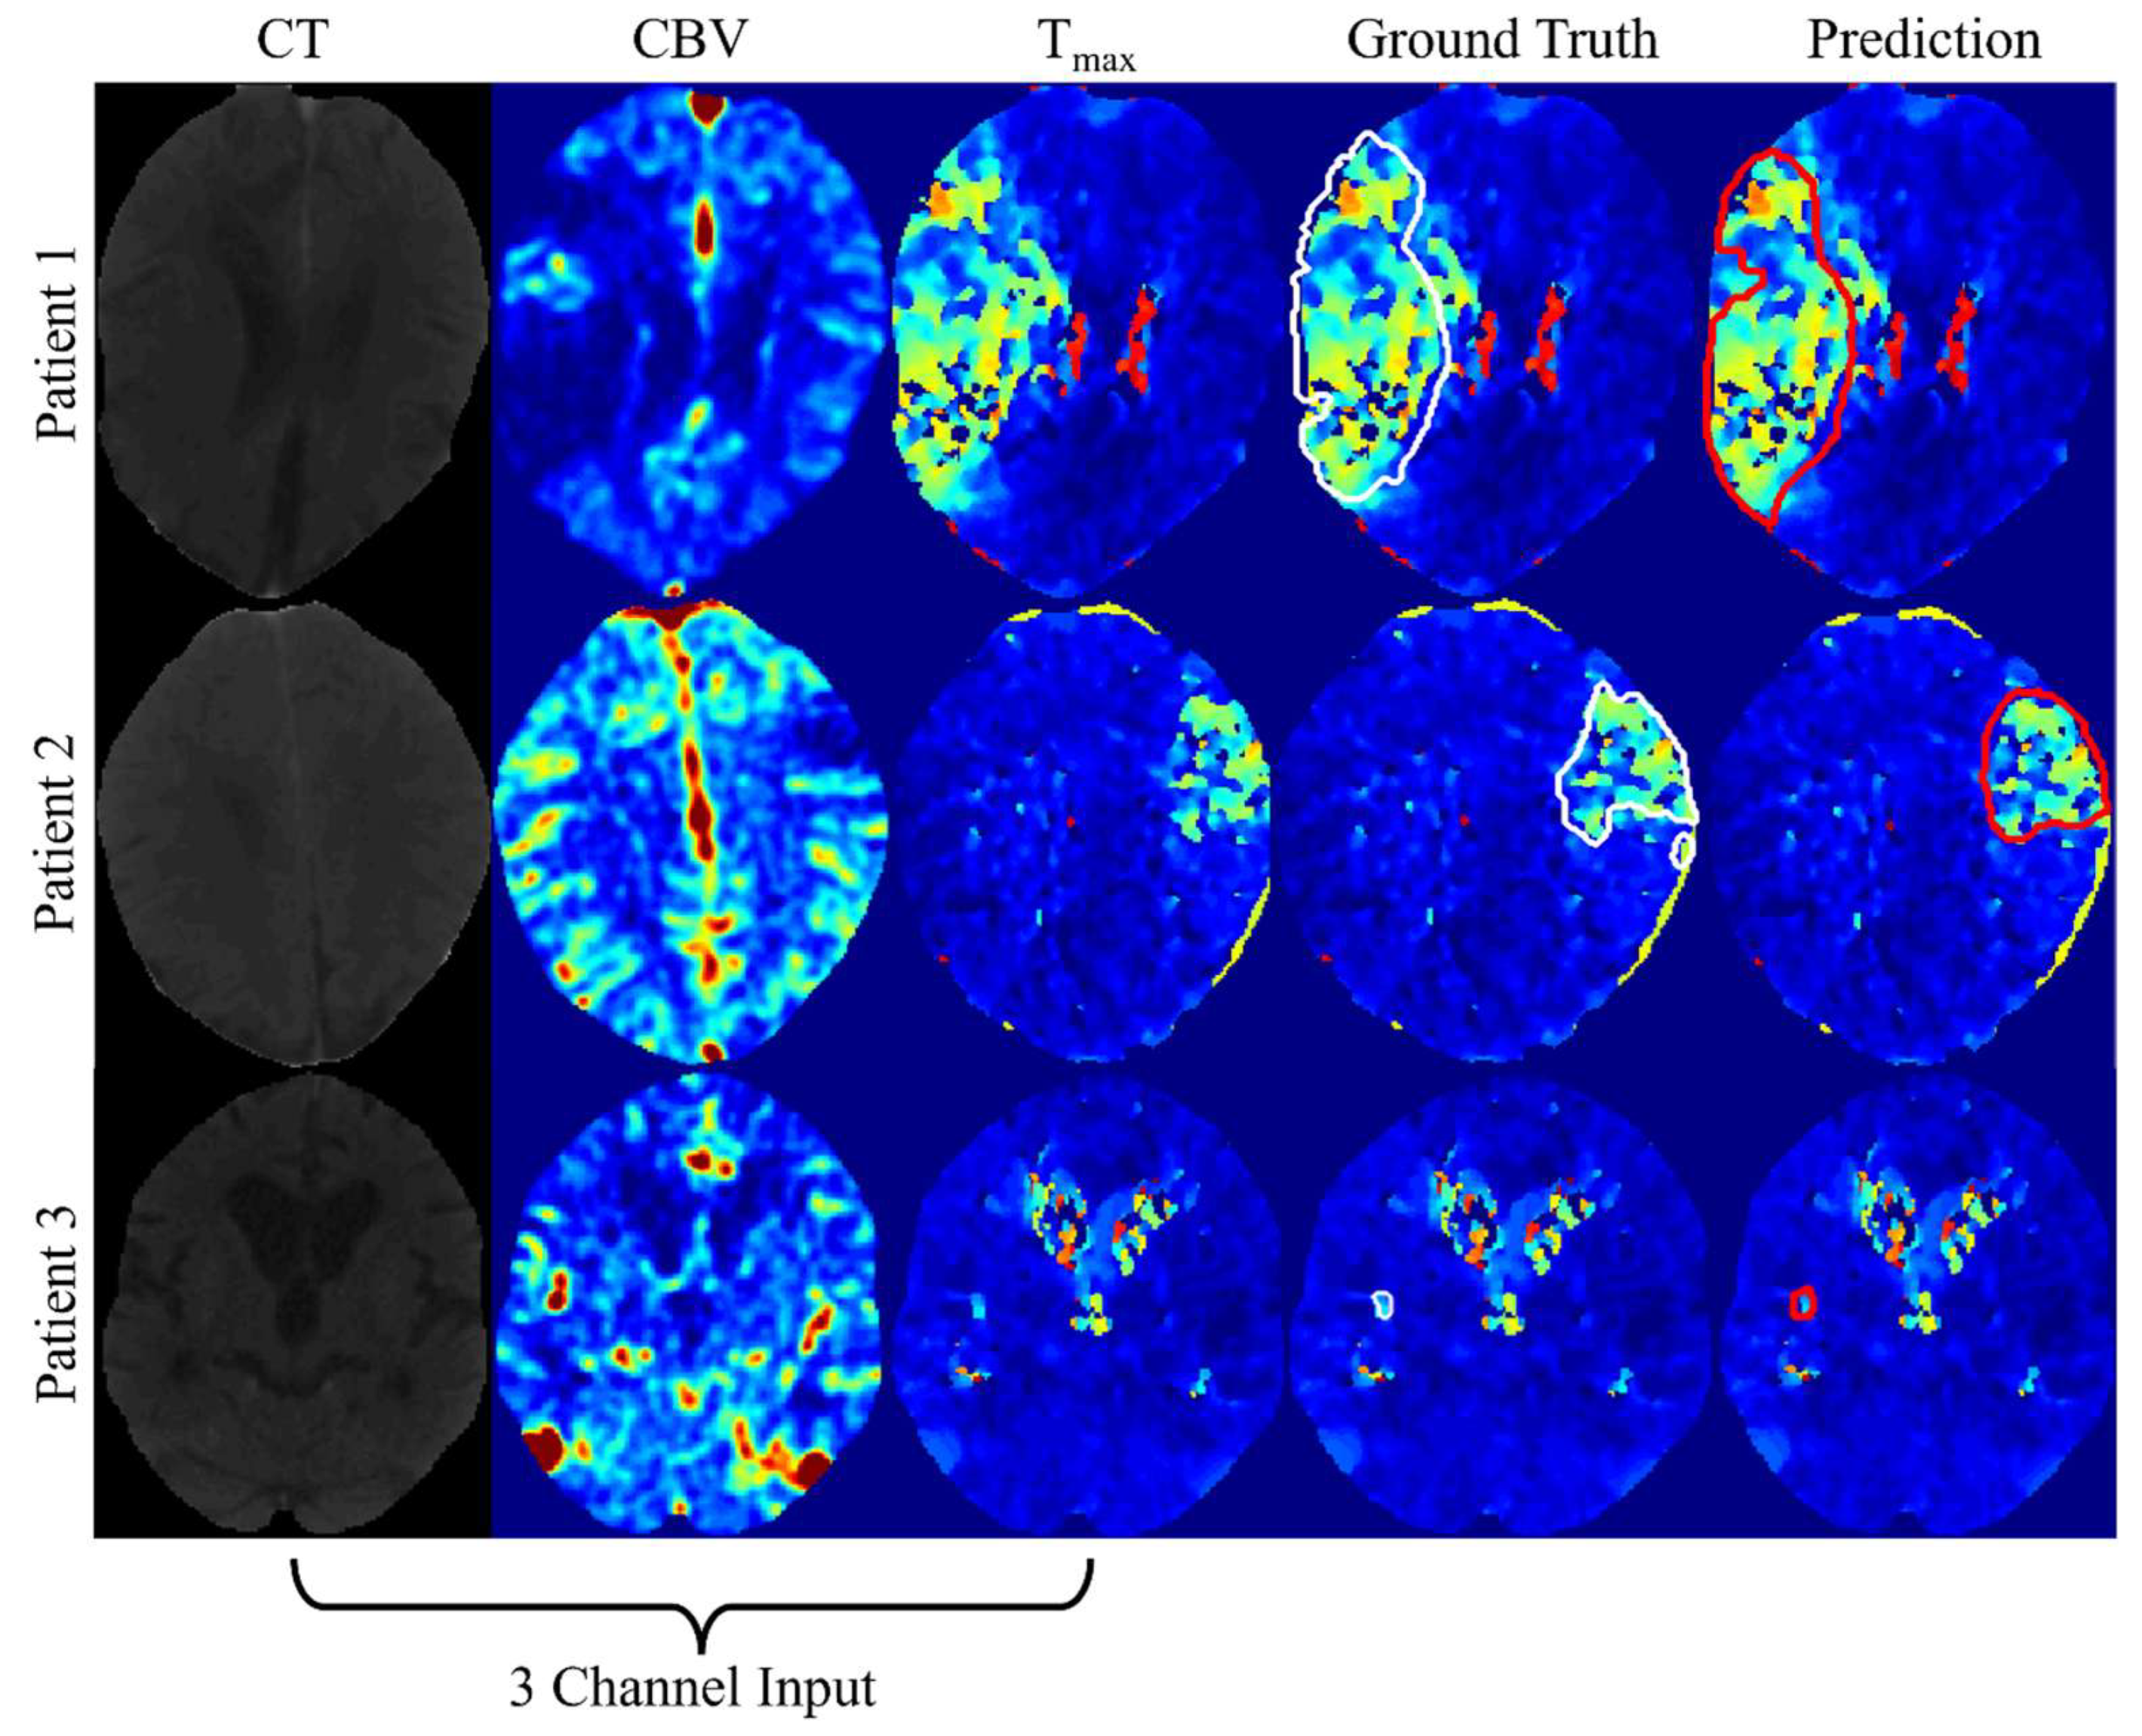

Using the CT, CBV, and Tmax image combination, with an initial dropout rate of 10%, the dice score was 0.71 ± 0.17 on the training set and 0.45 ± 0.32 on the testing set. When the dropout was increased to 25%, the dice scores remained similar, with 0.71 ± 0.17 on the training set and 0.44 ± 0.31 on the testing set. At 50% dropout, the dice scores decreased to 0.65 ± 0.19 on the training set, while the testing set score remained at 0.45 ± 0.32. Figure 4 shows the lesion mask predicted by the proposed network. Table 5 presents performance results for various architectural approaches, comparing training and testing dataset scores.

Figure 4.

Illustrates the predictions generated by the proposed DenseResU-NetCTPSS. The first column represents the CT images, the second column shows the CBV maps, and the third column shows the Tmax maps. CT perfusion maps are shown in pseudo-color to correspond to the quantitative nature of the maps. The fourth and fifth columns show the ground truth (white contour) and prediction (red contour) overlaid on the Tmax maps.